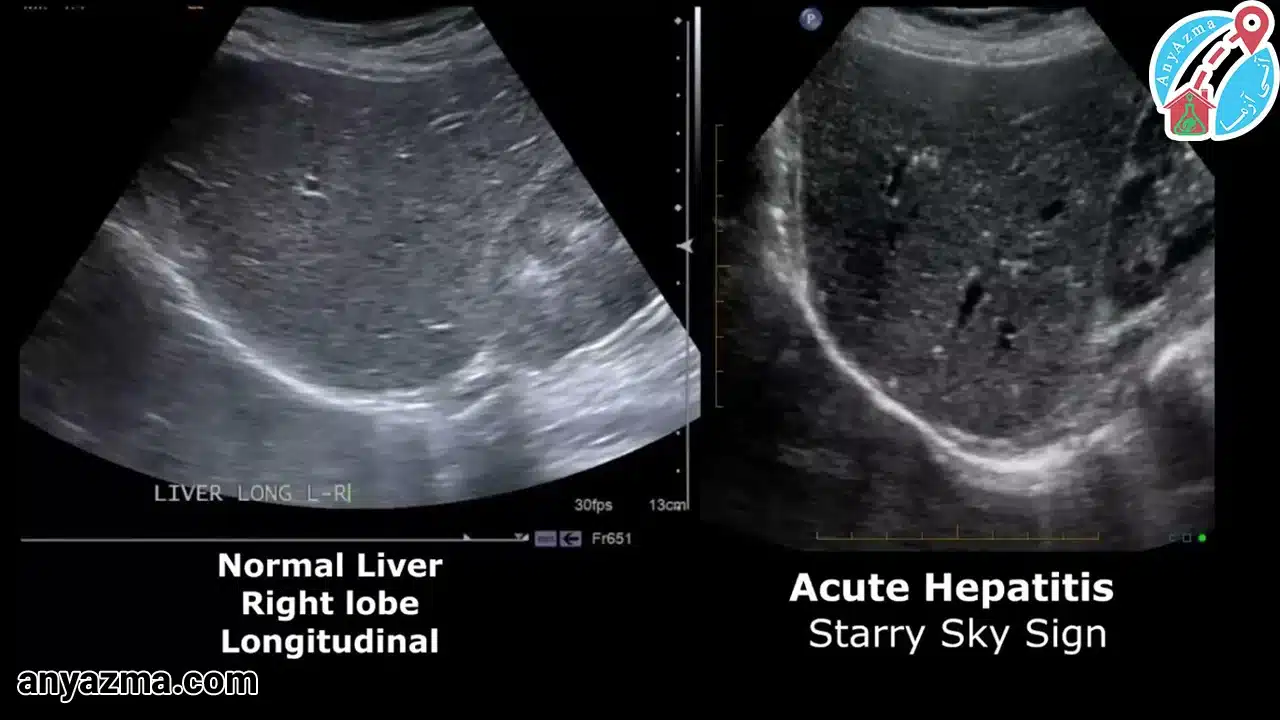

این رایجترین یافته غیرطبیعی است. وقتی کبد چرب (Hepatic Steatosis) وجود دارد، چربی باعث میشود بافت کبد روشنتر به نظر برسد. در برگه گزارش، این وضعیت به صورت کبد هایپراکو (Hyperechoic) یا کبد روشن (Bright Liver) توصیف میشود. رادیولوژیست این روشنایی را با کلیه راست مقایسه میکند؛ اگر کبد از کلیه روشنتر باشد، نشانه کبد چرب است. در مقابل، در هپاتیت حاد (التهاب)، کبد ممکن است بزرگ و «هایپواکو» (تیرهتر از حد معمول) به نظر برسد.

بله، التهاب حاد (هپاتیت) با تیره و بزرگ شدن کبد، و سیروز پیشرفته با بافت خشن (هتروژن) و سطح ناصاف (ندولار) قابل تشخیص است.